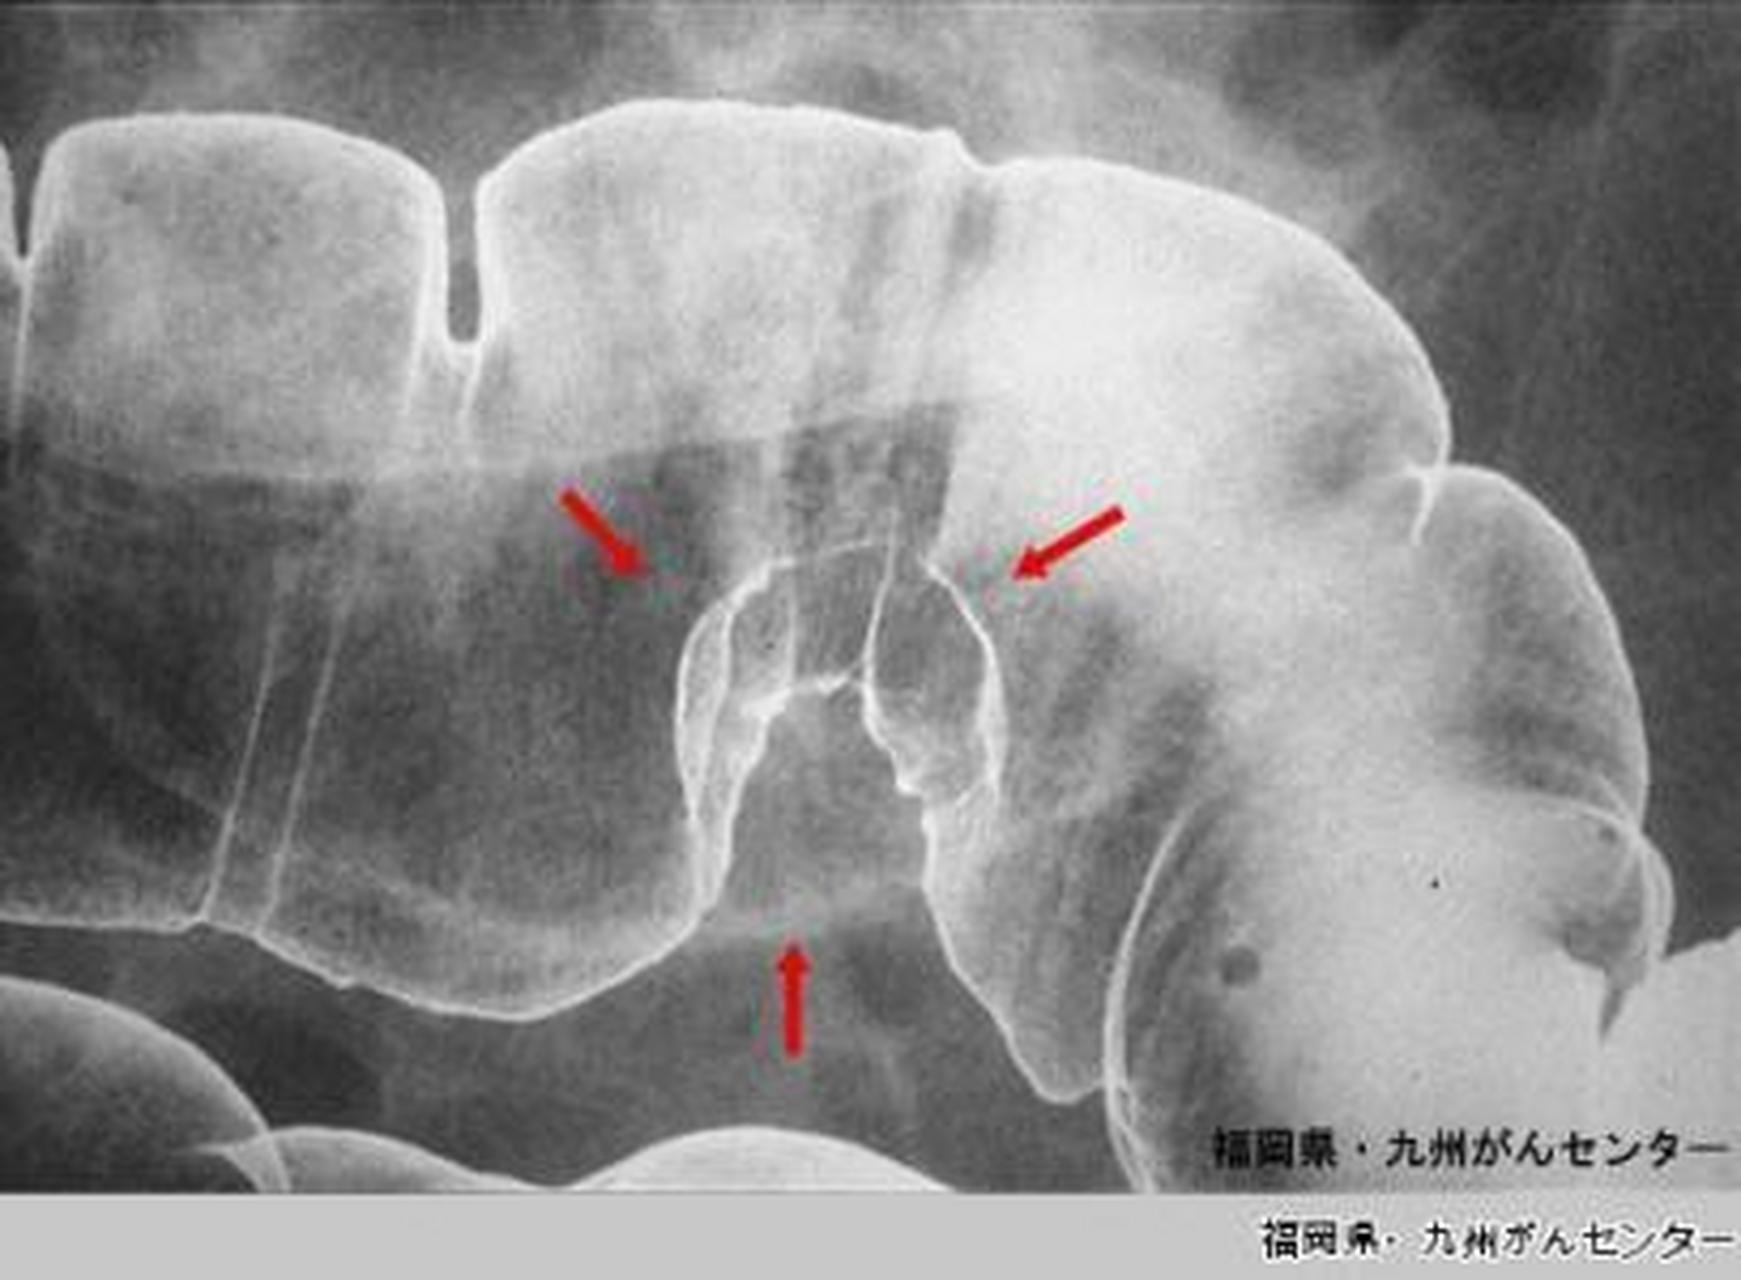

钡餐造影和胃镜的区别

1、胃镜和钡餐各有其独特的检查效果,无法一概而论哪个更好,具体取决于患者的临床症状和医生的检查需求胃镜的检查效果直观性强胃镜能够直接观察上消化道黏膜的细微变化,如充血糜烂水肿溃疡等准确性高对于疑似肿瘤息肉炎症等病变,...